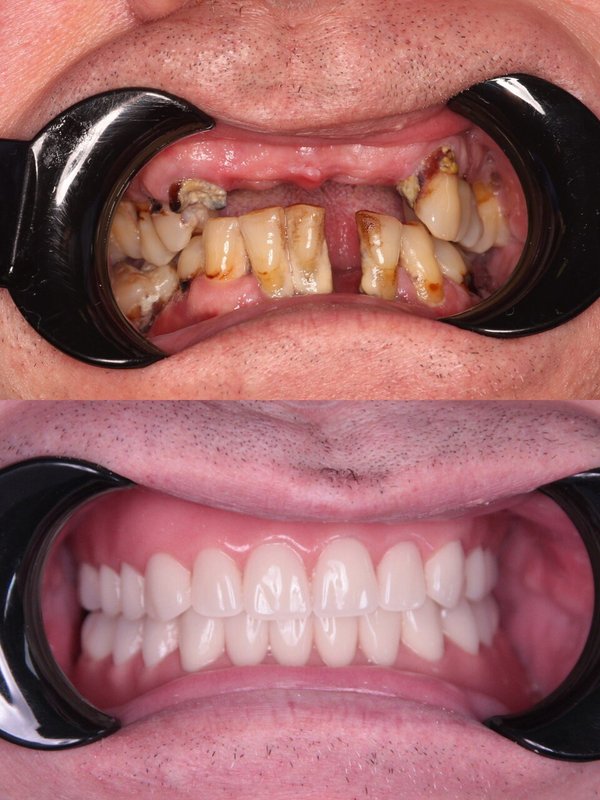

Фотогалерея

Если вы собираетесь добиться сияющей улыбки, то работу над ней лучше доверить экспертам. В стоматологической клинике Династия Н имеется специализированное оборудование для того, чтобы ваши зубы снова стали белоснежными. В нашей стоматологии оказывают услуги лечения кариеса, удаления зубов, компьютерной томографии, отбеливания, исправления прикуса, рентгенологической диагностики, изготовления имплантов, а также установки металлокерамики, брекетов, имплантов, виниров. С нами ваша улыбка будет яркой, а зубы крепкими!